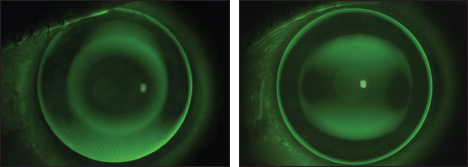

L'ortocheratologia è una tecnica non chirurgica e non invasiva per la riduzione reversibile della miopia, di alcuni casi di astigmatismo, di ipermetropia e di presbiopia, mediante lenti a contatto particolari, dette "a geometria inversa".

Allo stato attuale l'ortocheratologia può correggere molti difetti di vista, ma non tutti indiscriminatamente. I migliori risultati si possono ottenere per miopie fino a 6 dottrie; inoltre si conseguono eccellenti risultati anche per astigmatismi, presbiopie e ipermetropie.